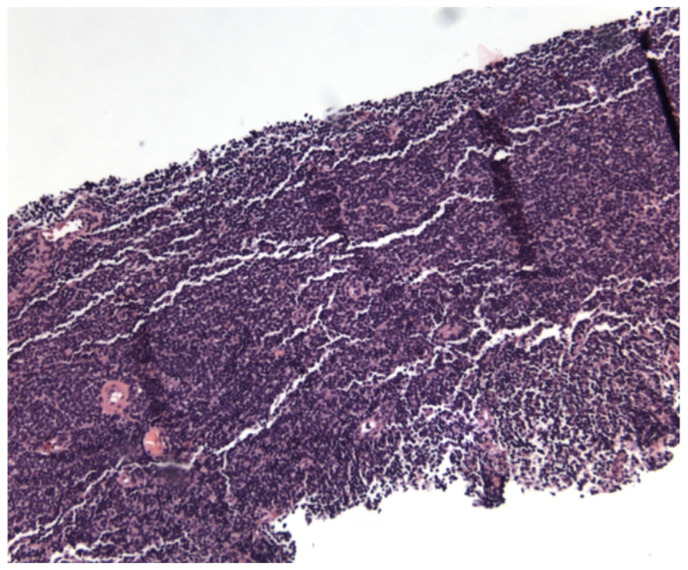

Marginal Zone Lymphoma in a Case of Hidradenitis Suppurativa Treated With Adalimumab Therapy.

Marginal zone lymphoma has seldom been described in relation to adalimumab used for treatment of hidradenitis suppurativa. Although studies have shown an increased risk of lymphoma with adalimumab, most of these studies were done in patients with underlying inflammatory bowel disease or rheumatoid arthritis where the disease itself presents as a confounder for lymphoma. Our case described adds to the role of chronic anti-TNF alpha therapy as a possible etiology of lymphoma.